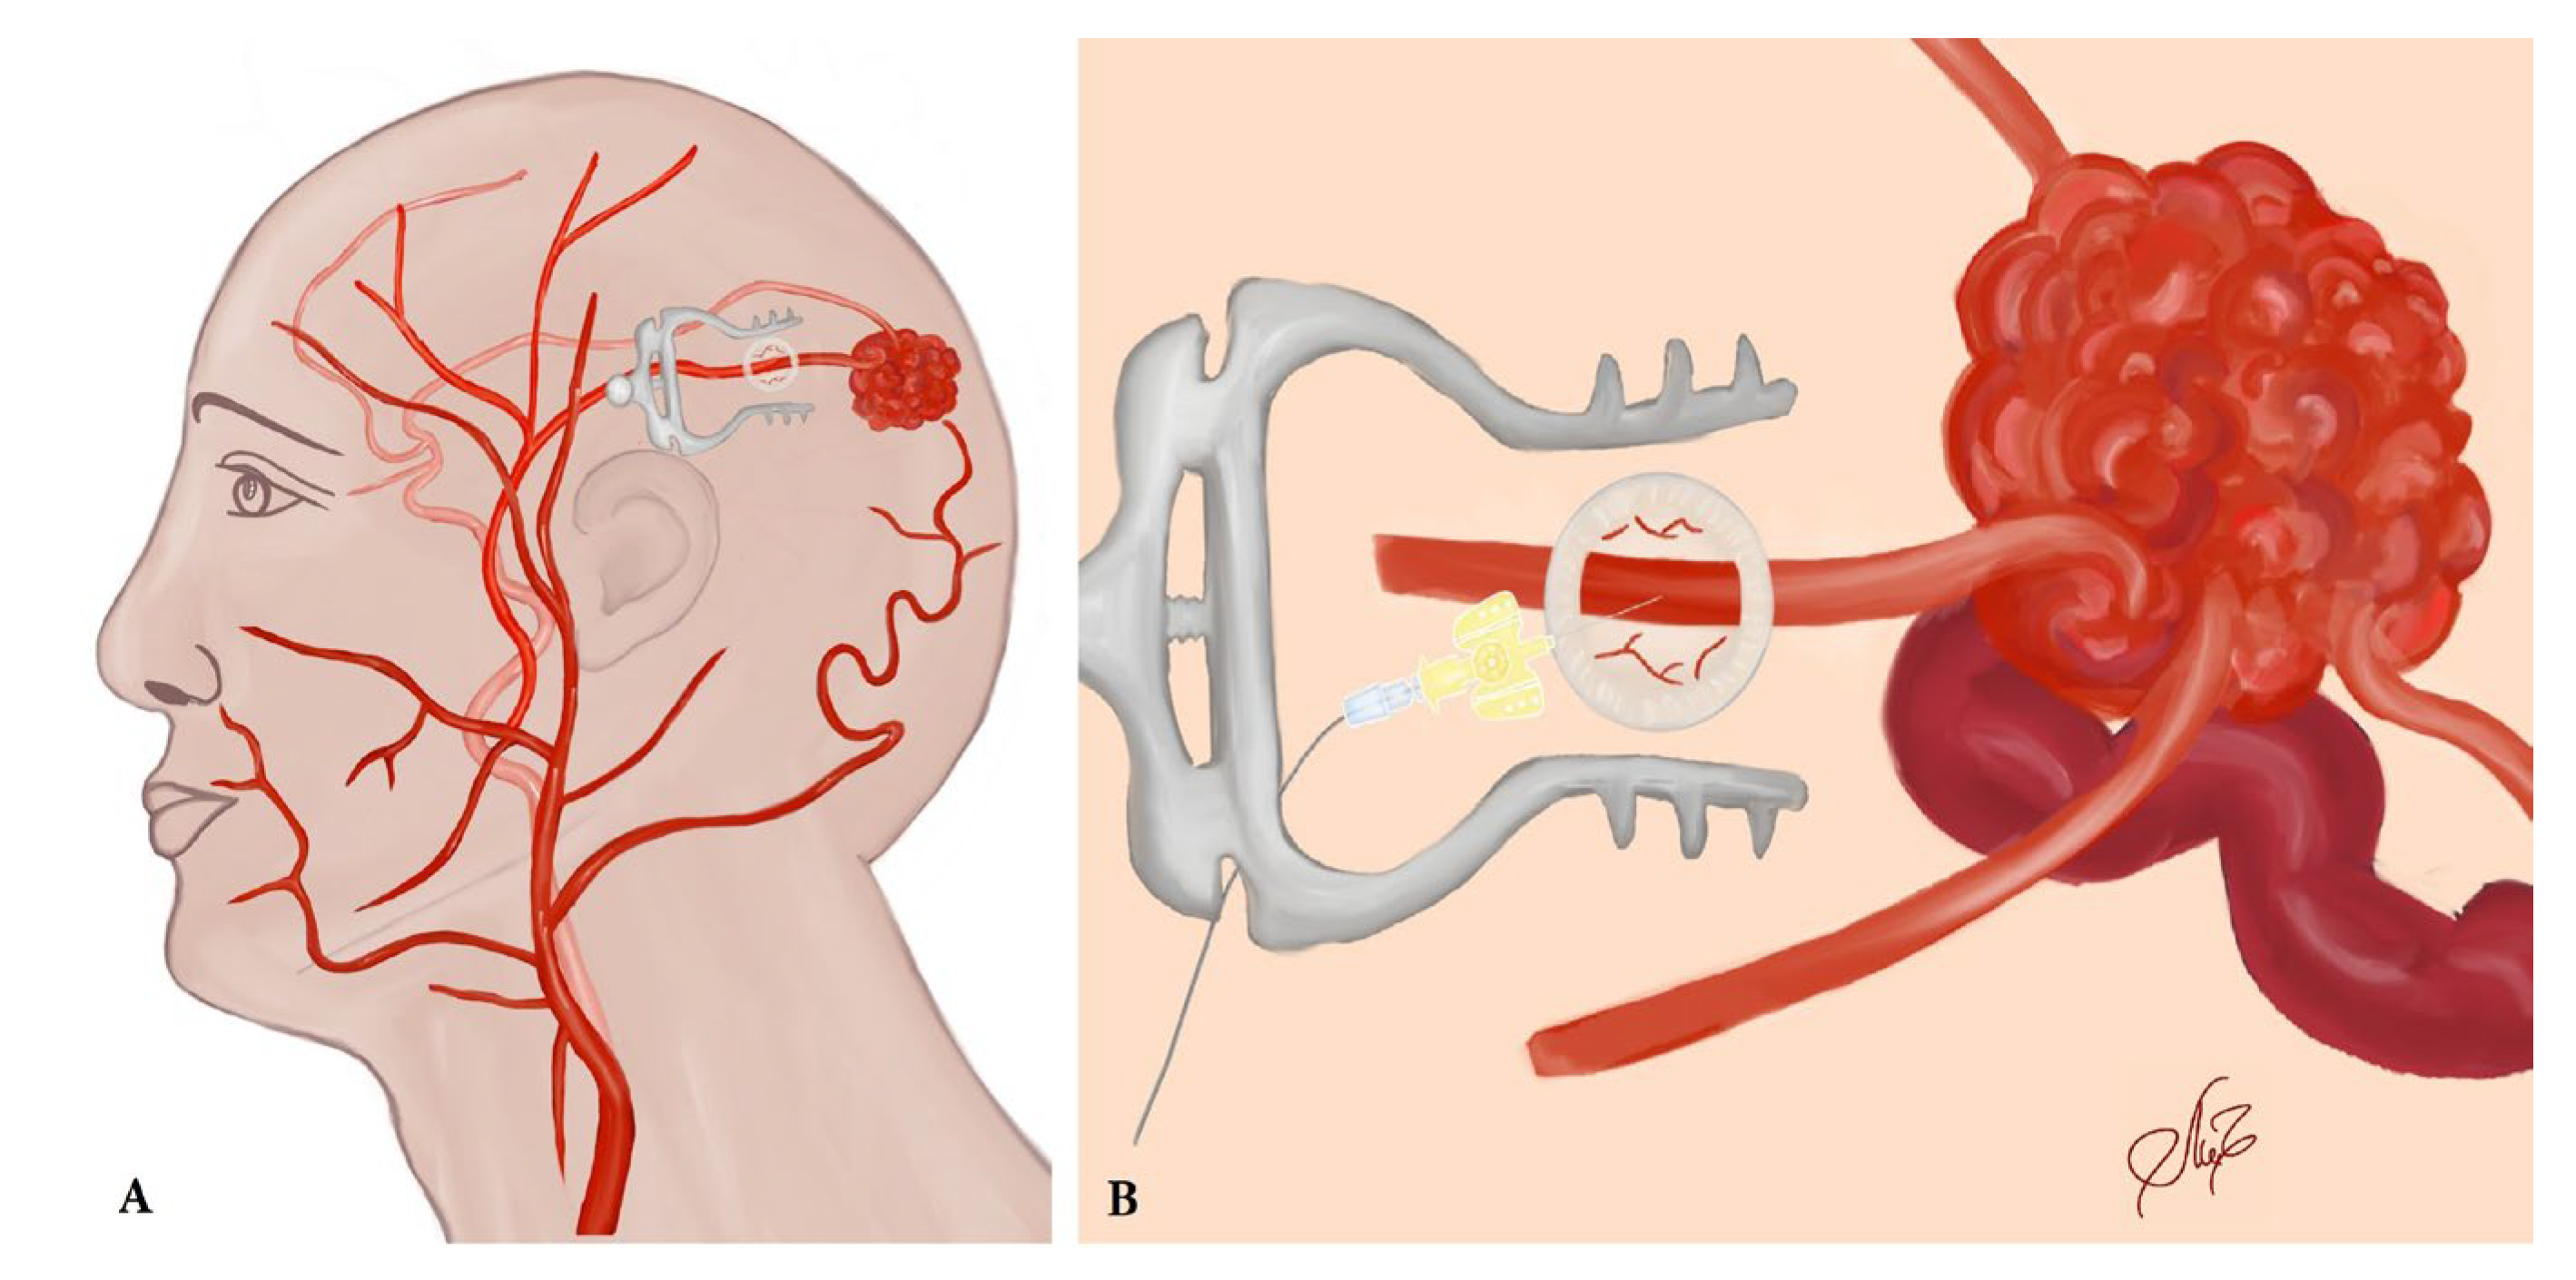

2.2. Treatment